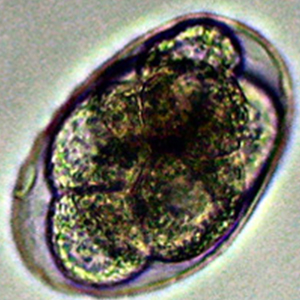

Les œufs de Necator americanus possèdent les caractéristiques morphologiques des œufs d’ankylostomes. Ils sont indifférenciables des œufs d’Ancylostoma à l’examen coproscopique (Strait et al., 2012).

Il comprend les nématodes du genre Ancylostoma et, de façon plus générale, tout œuf de strongle non embryonné.